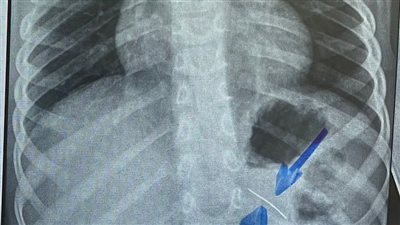

استخراج دبوس من معدة طفل بمستشفى سوهاج الجامعي